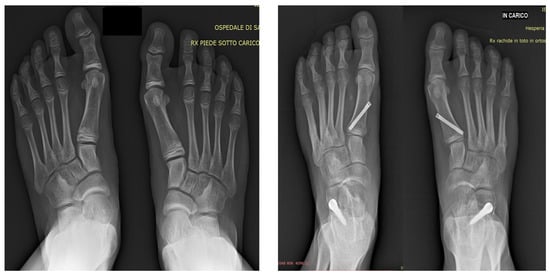

Simultaneous Correction of Juvenile Hallux Valgus and Flexible Flatfoot in Children: Outcomes of Combined First Metatarsal Hemiepiphysiodesis and Calcaneal-Stop Procedure

2.2. Surgical Technique

| Variable | Pre-Op | Post-Op | Mean-Difference (95% C.I.) |

|---|---|---|---|

| IMA (°) | 11.9 ± 1.3 | 9.3 ± 1.5 | 2.6 ± 1.7 (2.0–3.2) |

| HVA (°) | 22.0 ± 6.0 | 16.1 ± 3.6 | 5.9 ± 5.4 (3.8–7.9) |

| tTCA (°) | 27.3 ± 3.3 | 20.6 ± 3.5 | 6.7 ± 3.6 (5.2–8.3) |

| MA (°) | 18.8 ± 5.8 | 5.4 ± 4.8 | 13.3 ± 4.8 (11.4–15.3) |